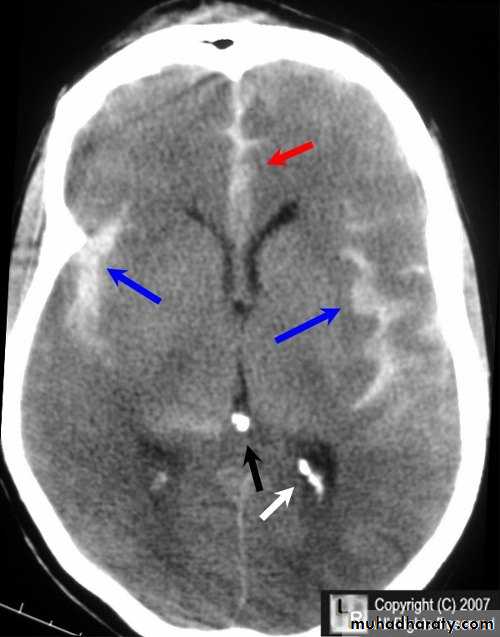

Acute subdural hematoma

Subacute subdural hematomaChronic subdural hematoma